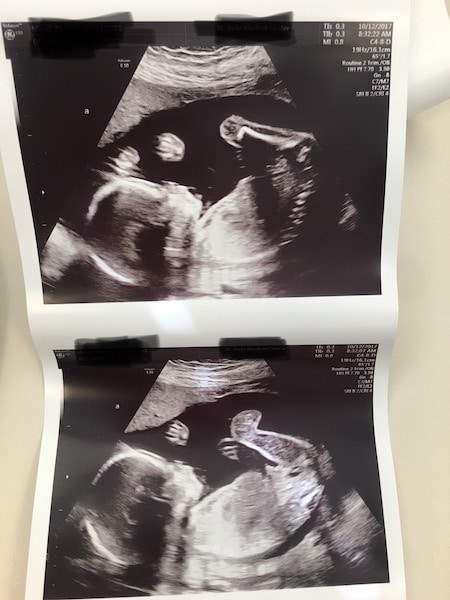

Ultrasound Photos at 21 Weeks Pregnant With Twins